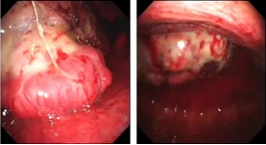

近年来,贵州航天医院各科室紧跟医学前沿,不断强技术、补短板,大力开展新技术、新项目,完成了许多高精尖、高难度、本地区“首例”的技术,填补了医院医疗技术空白,满足了群众日益增长的医疗需求。 贵州航天医院呼吸与危重症医学科是贵州省内呼吸疾病治疗规模最大,诊疗项目最全的呼吸疾病品牌科室,呼吸介入技术达到了全国先进水平,在贵州省内处于领先的地位。 本期,我们将为大家带来呼吸与危重症医学科特色技术——内科胸腔镜技术诊断和治疗胸腔疾病。 案例分享 患者苟某某,因劳累、气促,不明原因胸腔积液在某县一医院采取反复抽水等治疗手段效果不佳,当地医院考虑到患者年龄大(77岁),基础疾病较多,病情复杂,结合当地诊疗水平能力情况,建议转到上一级医院诊治,通过我院与该院建立的呼吸专科联盟绿色通道转入了我院。 患者入院后,呼吸与危重症医学科第一时间复查胸部CT,提示:右肺中叶、左肺感染,纤维化灶,左侧中量胸腔积液,右后侧胸膜轻度增厚,心包少量积液;并完善心电图、血常规、凝血功能、生化指标等术前检查。经科室专家团队集体讨论,得出患者左侧胸腔积液可能原因:结核?恶性?其他?冠心病、心功能不全、高血压病3级(高危组)、陈旧性肺结核复发?肺部感染;为进一步明确诊断,在充分评估、做好术前准备及应急预案、与患者及家属沟通的情况下,决定为患者进行内科胸腔镜检查术。 科室在患者入院第3天便实施了内科胸腔镜检查术,经检查取活检,病理不排除胸膜间皮瘤,送遵义医科大学附属医院病理会诊后诊断:胸膜间皮瘤。明确诊断后,科室专家团队为患者制定了个体化的治疗方案,患者病情很快得到有效控制,最终满意出院。半年后,医院通过电话回访,患者病情稳定,生活质量明显改善。 什么是内科胸腔镜 内科胸腔镜(medical thoracoscopy,MT)是一项微创诊断和治疗胸腔疾病的重要技术。主要应用于无创方法不能确诊的胸腔积液和胸膜疾病,通过局部麻醉后在胸壁做一个小切口,插入胸腔镜,直接观察胸膜、肺表面、纵隔等部位的病变情况,可进行活检、粘连松解及胸膜固定等操作。具有创伤小、恢复快、诊断准确性高等优点。 内科胸腔镜原理 内科胸腔镜是一项利用现代光学技术和成像技术的侵入性操作技术,应用电子支气管镜、硬质或软硬结合(半硬)的胸腔镜的一种电子内窥镜,末端装有连接着显示屏的微型摄像头。通过胸壁1-2cm左右的小切口,将内科胸腔镜及专用器械(戳卡套管)通过小切口进入胸腔,微型摄像头将胸腔内的情况投射到显示屏幕上,医生可以通过镜头全面、直观地观察患者胸腔内情况,了解胸膜病变确切位置和形态改变,还可对胸膜上的病变进行活检及治疗的操作技术,安全、微创、几乎无痛地“揭秘”不明原因的胸腔积液。 内科胸腔镜技术优势 (一)安全性高:仅需局部浸润麻醉,并发症发生率相对较低,对患者的身体条件要求较低。 (二)操作简便:操作时间短,痛苦少,患者耐受好。 (三)微创性:切口小,对患者身体损伤小,术后疼痛轻,恢复快。 (四)高分辨率成像:清晰显示胸腔内细微病变,提高诊断准确性。 (五)可直视操作:直接观察病变,进行精准活检和治疗。 (六)适用范围广:可用于不明原因胸腔积液、胸膜疾病、肺部疾病等的诊断和治疗。 (七)费用低:与外科胸腔镜比较费用低廉。 内科胸腔镜技术是贵州航天医院呼吸专科和呼吸介入诊疗优势的一部分,在2016年率先开展了内科胸腔镜技术,年手术量约100余例,已建立了快速、精准、规范、有效的一体化诊疗服务体系。目前呼吸与危重症医学科内科胸腔镜技术广泛应用于不明原因胸腔积液、气胸、脓胸的诊断和肺癌、弥漫性恶性胸膜间皮瘤等的分期,恶性或复发性胸腔积液、早期脓胸、自发性顽固性气胸的治疗。 镜下常见表现:单发或多发结节、灰白色弥漫性粟粒样结节、胸膜充血、水肿、胸膜增厚及纤维分隔或粘连带形成。 诊断方面: 胸腔积液的病因诊断。内科胸腔镜对恶性胸腔积液的诊断率可高达90%以上,胸腔镜对结核性病变诊断率极高,几乎达到96%以上。 腺 癌 恶性淋巴瘤 软骨肉瘤胸膜转移 滑膜肉瘤胸膜转移 结核性胸膜炎 治疗方面: 脓胸 肺大泡 贵州航天医院 呼吸与危重症医学科学科带头人 廖江荣 国务院政府特殊津贴专家 二级教授 主任医师 贵州航天医院副院长 国家级学术任职: 第二届中国医药教育协会介入微创专业委员会呼吸分会副主任委员 中国抗癌协会肿瘤微创治疗专业委员会常务委员 中国防痨协会结核病转化医学专业分会常务委员 第一届中国人体健康科技促进会呼吸介入专委会常务委员 中国医疗保健国际交流促进会结核病学分会第三届委员会常务委员 中国抗癌协会肿瘤微创治疗专业委员会粒子治疗学组第四届委员会委员 中华医学会结核临床专业委员会内镜介入委员 中华医学会放射学分会第十五届委员会介入学组呼吸系统介入专业委员会委员 北京健康促进会中青年专家委员会胸部疾病精准活检分委会副主任委员 中国医师协会介入医师分会第二届委员会肿瘤消融专业委员会委员 中国结核病防治综合质量控制专家指导委员会委员 亚洲冷冻治疗学会常务委员 世界内镜医师协会呼吸内镜协会常务理事 内镜临床诊疗质量评价专家委员会委员 “西部呼吸介入联盟”副理事长 专业擅长: 贵州航天医院 呼吸与危重症医学科简介 贵州航天医院呼吸与危重症医学科以呼吸危重症和介入呼吸病学为强力推手,以肺部感染性疾病及肺癌、肺小结节的早期精准诊疗、慢性呼吸疾病康复治疗为特色,以人才团队建设为核心的科室发展模式,现已成为省内呼吸疾病治疗规模最大,诊疗项目最全的呼吸疾病品牌科室。是贵州省医学重点学科、临床医学重点专科建设单位,遵义市首批呼吸重点学科、重点专科建设单位。是国家卫健委能力建设和继续教育肿瘤微创介入建设中心、贵州省县级医院微创介入培训中心、遵义市呼吸疾病临床医学中心。是国家呼吸医疗质量控制与管理哨点医院、遵义市呼吸内科专业医疗质量控制中心。是中国医药教育协会介入微创呼吸分会呼吸介入技术培训中心单位;国家卫健委海医会呼吸分会ROSE专委会“诊断性介入肺脏病学快速现场评价”培训基地;中国肺癌防治联盟“贵州航天医院肺结节诊治”分中心,中国人体健康科技促进会呼吸介入技术培训基地,贵州省中西医结合会呼吸学分会呼吸介入专委会主委单位。 基本情况 平均每年开展气管镜诊疗约4000例,经皮肺穿刺介入诊疗近千例,开展的项目包括经支气管镜(软、硬)下冷冻、氩气刀、高频电刀、球囊扩张、支架置入、超声内镜诊疗等气道介入诊疗技术,经皮肺穿刺活检及肿瘤消融术(微波、冷冻)、ROSE技术、内科胸腔镜诊疗及经血管介入诊疗技术,且多项呼吸介入诊疗技术在省内处于领先水平。 诊疗范围 航天医院呼吸专科擅长:致力于呼吸系统感染性、疑难性疾病的介入快速精准诊疗;肺癌与肺小结节早期精准诊疗水平项目提升。擅长于呼吸系统(肺)疑难病的诊断及危重病的救治,尤其在肺癌、肺小结节的早期诊断;肺癌综合靶向治疗;肺结核综合诊疗;肺部疾病的介入诊疗在省内处于前沿水平。 咨询热线 (一)呼吸与危重症医学科一病区 医生办公室:27677317 护士站:28614217 (二)呼吸与危重症医学科二病区 医生办公室:28691274 护士站:28690442 (三)呼吸与危重症医学科三病区 医生办公室:28692417 护士站:28690461 (四)呼吸与危重症医学科四病区 医生办公室:28616402、27677582 护士站:28614987、27677862